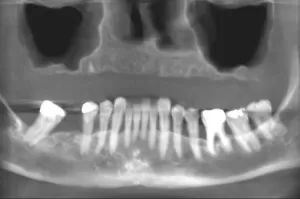

Implant nha khoa đã giải quyết phần lớn các trường hợp mất răng từng phần hoặc toàn bộ ở hàm trên & hàm dưới :

Từ trước đến nay, chúng tôi đã áp dụng kỹ thuật “All on 4” cho nhiều trường hợp mất răng toàn bộ ở hàm trên với thiếu hổng xương nhiều ở hai bên hàm đã mang lại kết quả điều trị rất tốt cho bệnh nhân. Tuy nhiên, ở một vài trường hợp, vì sự thiếu hổng xương trầm trọng, việc phục hình sau đó đã bị giới hạn về số lượng răng và sức nhai của bệnh nhân, làm bệnh nhân chưa được hài lòng.

Hãng Nobel Biocare một lần nữa đã nghiên cứu và đưa ra giải pháp dùng Zygoma Implant để gắn Implant vào xương gò má để giải quyết được những trường hợp mất răng toàn bộ ở hàm trên với thiếu xương nghiêm trọng do xoang hàm lớn, vùng xương ổ răng bị tiêu xương trầm trọng.